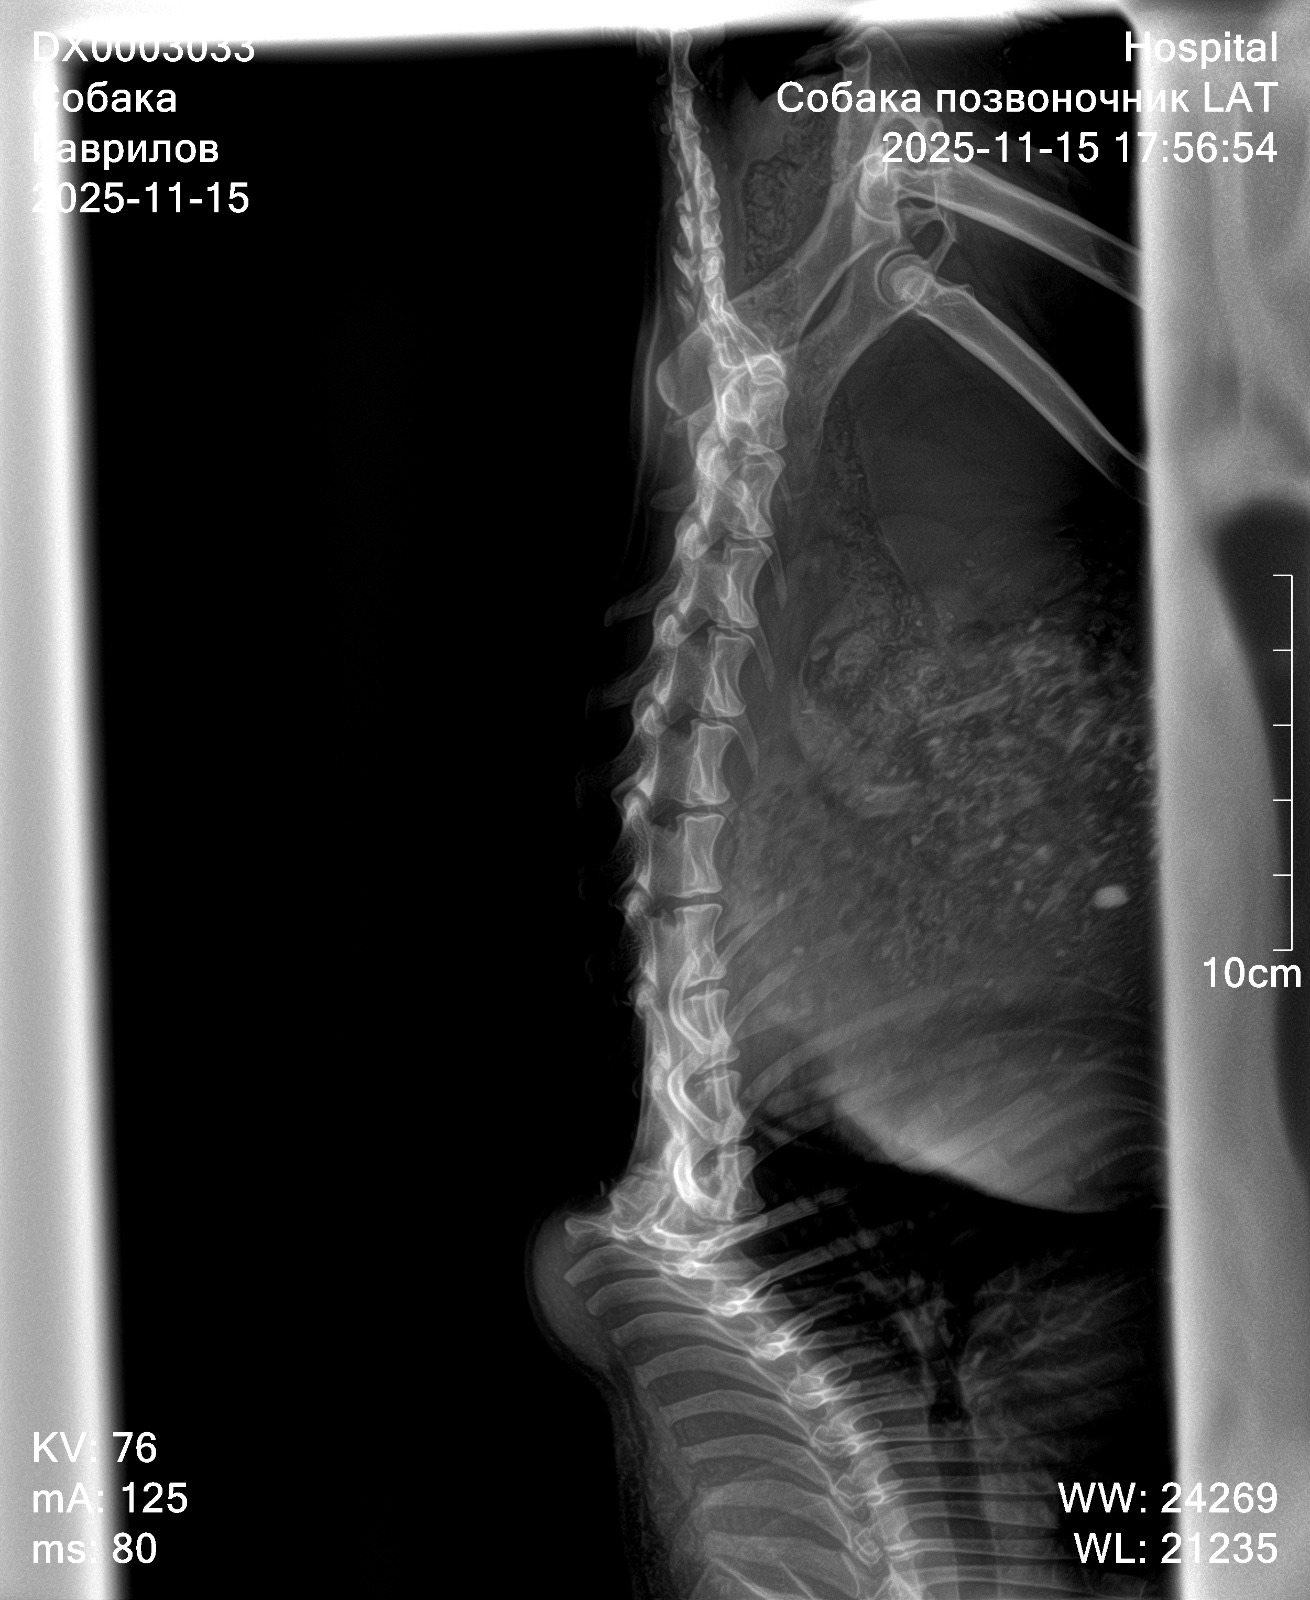

Сегодня подобрали на обочине собаку, она ползла и волокла за собой задние лапы😭думали перелом лап, оказалось, перелом позвоночника и в связи с этим отказали задние конечности. Врач сказал, что перелому несколько месяцев, уже всё срослось, поэтому в операции смысла нет, собака-инвалид. На фоне этого могут быть проблемы со стулом и мочеиспусканием, мы пока не успели этого заметить. Задние лапы стёрты в кровь из-за того, что повсюду волочет за собой по камням и земле😭